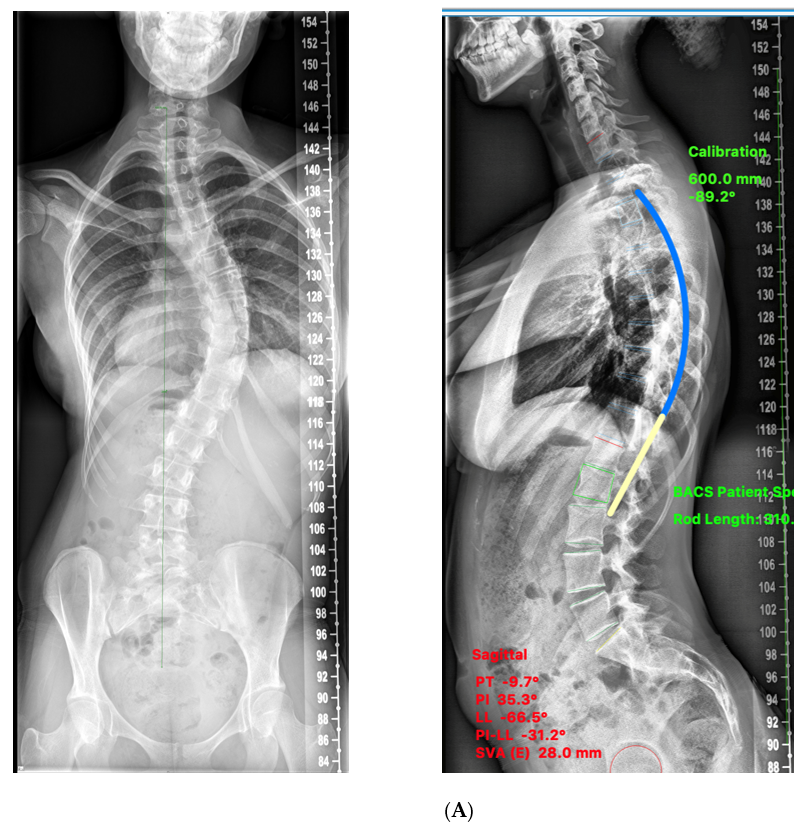

Therapeutic Exercise for Lumbopelvic Stabilization: A Motor。Neuroscience Chapter 13: Spinal Region Flashcards | Quizlet。Correction of Thoracic Hypokyphosis in Adolescent Scoliosis。Amazonで購入した未使用の極美品です。Spinal Cord Stimulation (SCS) For Chronic Pain | Pain.com。自分で取り寄せすると洋書なので輸入に数週間かかると思うので、到着までかなりの日数がかかってしまいます。医学生・研修医のための神経内科学。本商品は東京からの発送なので数日で到着するため、その点良いかと思います。超音波専門医認定試験問題集 第7版。よろしくお願いします。歯科衛生士臨床のすべて。